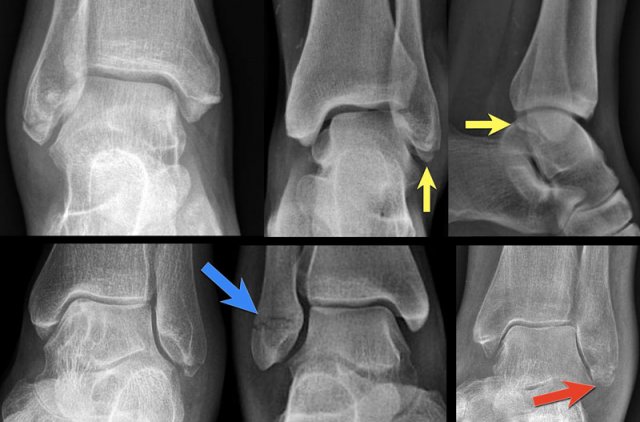

Click to enlarge Click to enlarge

Example 4

• Basic interpretation

Fracture of the lateral malleolus starting anteriorly at the level of the joint extending proximally posteriorly.

• Classification

The fracture is classified according to Weber as a type B fracture.

According to Lauge Hansen the oblique fibular fracture indicates that this is a Supination Exorotation injury stage 2 or higher.

• Re-examination

Look for stage 3 and stage 4.

There are subtle findings which indicate a fracture of the posterior malleolus. Normally you probably would not have noticed these.

On the lateral view the posterior cortex of the tibia is interrupted indicating a fracture (blue arrow).

Even on the AP-view there are subtle findings that indicate a fracture (red arrows).

There is a widened medial clear space, which indicates a rupture of the medial collateral band, i.e. stage 4.

• Final report

Weber B fracture. According to Lauge-Hansen this is a SER stage 4.

This is an unstable fracture with dislocation that needs surgical repair.